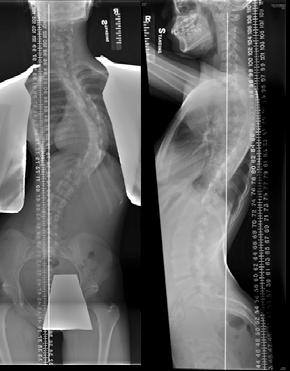

Idiopathic scoliosis accounts for 80-85 % of cases [1]. The spine is normal at birth but develops a deformity in childhood. It can occur in toddlers and young children, but the majority of cases occur from age 10 to 15 (Figs. 1 and 2). 2-3% of adolescents have scoliosis. Boy and girls are equally affected by small curves, but girls are eight times more likely to develop progressive curves. According to recent research, about one in three children whose parents have scoliosis will develop scoliosis. Scoliosis is considered a partially genetic condition. However, exactly which genes cause scoliosis is unknown [2,3]. It’s a common believe that scoliosis causes significant back pain and functional disability. In fact, mild to moderate scoliosis typically does not cause back pain and will not cause compression onto the nerves or the heart and lung. Only very severe scoliosis curves will cause heart and lung problems [1].

Fig. 1A Typical right thoracic scoliosis showing a curved back, tilted shoulder, prominent scapula, and trunk listing. |

![]() Fig. 2 AP & Lateral radiograph of the same patient. |